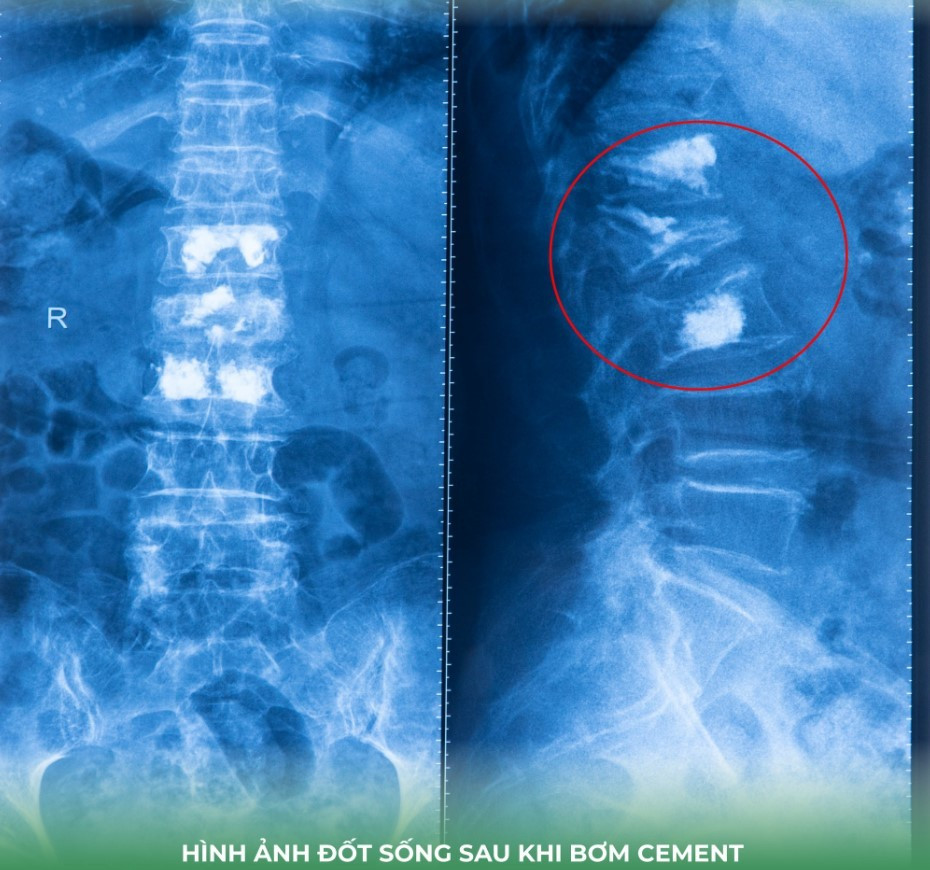

Sau khi hội chẩn, các bác sĩ quyết định điều trị giảm đau cột sống bằng phương pháp tạo hình thân đốt sống bằng bơm cement sinh học giúp cố định thân đốt sống bị xẹp, cải thiện tình trạng giảm đau nhức, phục hồi vận động sớm và hạn chế biến chứng do nằm lâu, đặc biệt phù hợp với người cao tuổi.

Ca phẫu thuật được thực hiện an toàn, chính xác bởi đội ngũ bác sĩ có chuyên môn: BS.CKII. Lý Tấn Phát – Phó trưởng Khoa ngoại tổng hợp, BS.CKI. Thông Minh Vừa, BS Huỳnh Hoàng Khang cùng ê-kíp khoa gây mê hồi sức. Ca bệnh được thực hiện trong quy trình chuyên môn chặt chẽ, bảo đảm an toàn cho người bệnh, theo tiêu chuẩn kiểm định quốc tế AACI (Hoa Kỳ).

Sau phẫu thuật, tình trạng đau lưng của cụ bà giảm rõ rệt, cải thiện vận động xoay trở, đi lại, ngồi tốt hơn. Tuy nhiên là bước đầu của điều trị giảm đau, điều trị bằng thuốc loãng xương mới quan trọng vì đây là nguyên nhân chính.